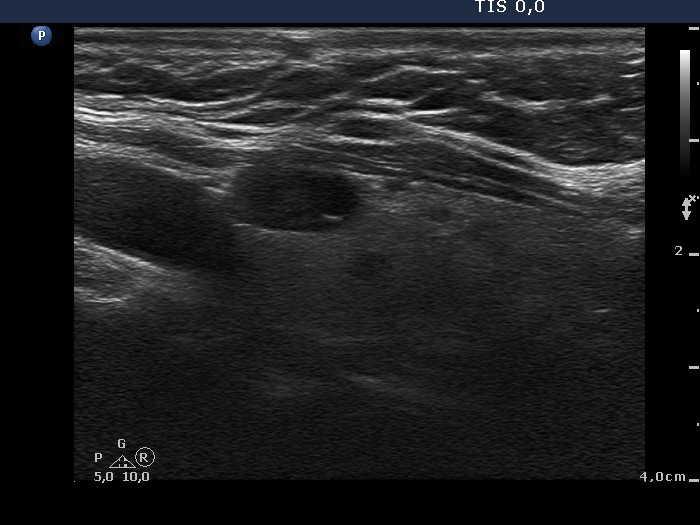

Follicular adenoma (histological diagnosis)

After aspiration of 2 mL cystic fluid |

|

It became more evident after removal of the cystic fluid that the figures are comet-tail artifacts.